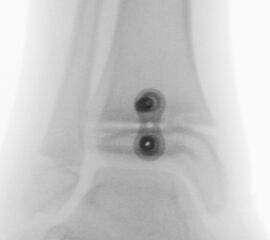

Knick-Senk-Platt-Fuß Korrektur mit dem Canalis Tarsi Spacer

In der Korrektur des schmerzhaften, aber flexiblen Knick-Senk-Fußes oder Plattfußes ist die Schraubenarthrorise mit einem Sinus tarsi oder besser bezeichnet als Canalis tarsi Spacer und alternativ mit einer Calcaneus-Stopp-Schraube seit vielen Jahren ein etabliertes Verfahren und führt zu einer kompletten Korrektur von flexiblen Knick- und Plattfuß-Fehlstellungen (Abb. 7). Die nötige Schnittlänge über dem Sinus tarsi beträgt für beide Verfahren 1 cm.